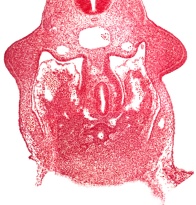

Preparation for microscopic examination

Heart